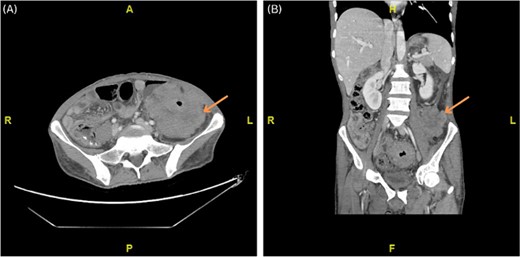

Abdominal CT scan with IV contrast displayed marked non-uniform wall thickening and nodularity with heterogeneous enhancement involving the mid rectum extending proximally to the splenic flexure of the colon, and multiple small size loco-regional lymphadenopathies (Fig. 1). Additionally, positron emission tomography (PET) scan displayed intense radiotracer uptake in the rectal, sigmoid and left colonic mass/wall. Further diagnostic evaluation included colonoscopy which revealed a rectosigmoid polyoid, friable, stricture-like, lesion, around ~15 cm in length (starting from 10 cm from anal verge and extending 25 cm upwards). Histopathology examination of the colonoscopy biopsies was inconclusive.

(A, B) Axial and coronal computed tomography (CT) scan showing marked non-uniform wall thickening and nodularity with heterogeneous enhancement invading the lateral part of the left psoas muscle and the left transverse abdominis muscle.